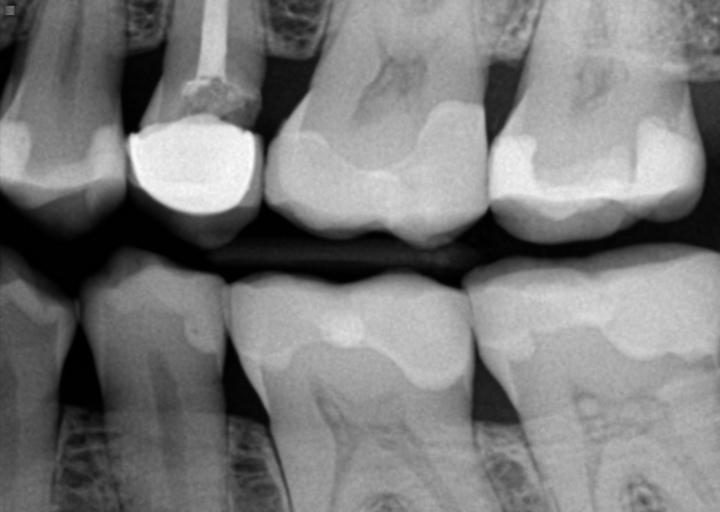

If you remove the crown from a tooth, it must be replaced or the tooth must be removed. When a tooth is prepared for a crown, the enamel (protective layer) is removed, exposing the underlying tooth structure, dentin. Dentin is very sensitive and much softer than the enamel shell. Therefore it can decay rapidly. Crowns that fit well do not harbour bacteria and odors, nor will it cause other teeth to decay. Poor oral hygiene will allow caries to form, along with a high intake of carbohydrates in the diet. Some prescription medications can also alter the pH in the mouth making one more carious prone. If there is decay under the crown, that could also be the culprit of your bad breath. The only way to properly have a diagnosis is to have a full set of dental x-rays taken along with a comprehensive examination including a periodontal charting. This will evaluate your teeth and gums, diagnose the source of the bacteria and properly plan how to restore you to health.